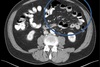

Why do we have this color inside the peritoneal cavity?

A

There is fluid in it: ASCITIS